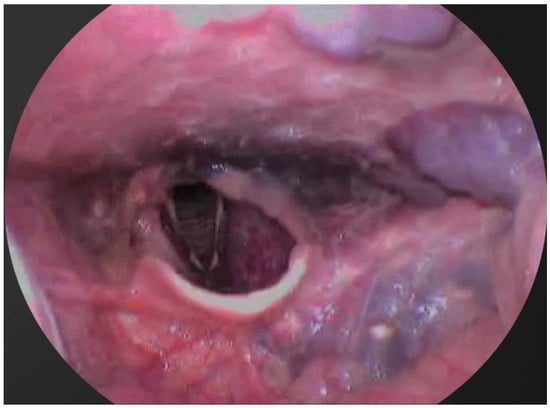

- The third case involved a 47-year-old female who developed localized mucosal necrosis secondary to a hematoma, which was associated with significant tenderness. The patient managed the condition with local wound care, and the lesion healed completely within 11 days without the need for systemic therapy (Figure 10).